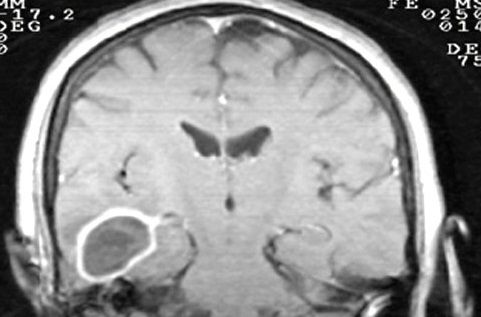

1. Neoplasias

1. lesiones expansivas benignas o cancerosas, cuyas células se multiplican de manera irrestrictiva y forman una masa dentro de la cavidad craneal o raquídea.

1. Dependiendo de su localización y sus cualidades, entre los mas frecuentes: gliomas, meningiomas y adenomas hipofisiarios.

1. Pueden ser primarios al originarse del SN que pueden ser benignos o malignos con caracteristicas infiltrativas y proliferativas causando alteraciones funcionales o secundarios por metástasis

1. Pueden generar alteraciones en algunos de sus 3 componentes: encefalo (1400ml), LCR (140ml) y sangre (150ml)

1. Si el tumor crece en el encefalo comprime y destruye al parenquima y desplaza al LCR y a la sangre aumentando la presión intracraneal. Si el crecimiento es lento, se da una adaptación con cambios de flujo sanguineo ( el tejido tumoral comprime venulas del tejido adyacente)

1. Si la adaltación se pierde por completo se da el desplazamiento y manifestaciones de compresion como cefalea, vómitos y edema papilar.